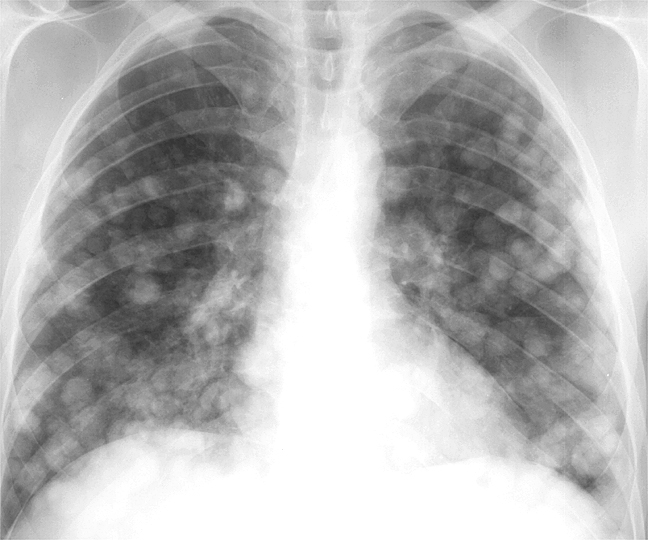

Рентгеновские снимки опухоли Панкоста